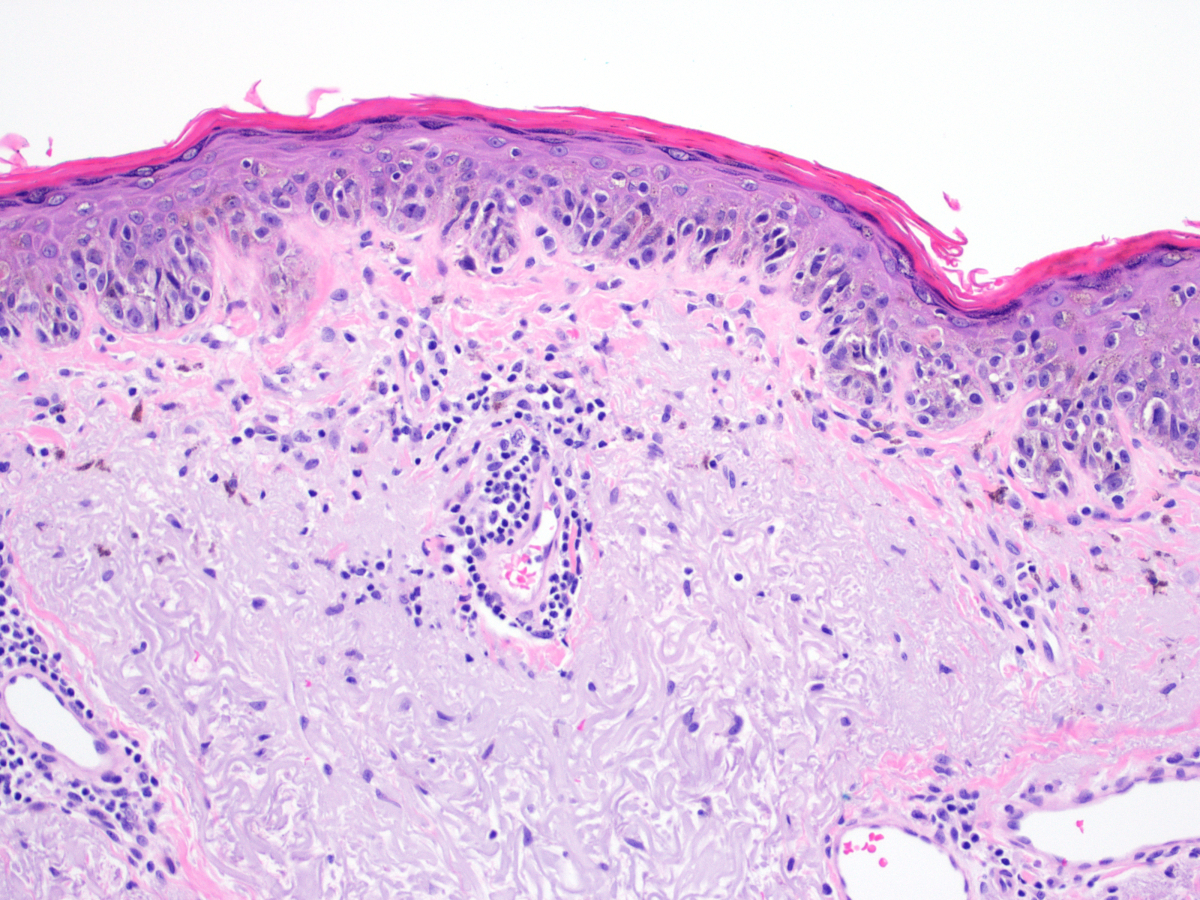

Microscopic (histologic) description

- Proliferation of intraepidermal (single and nested) melanocytes overlying solar elastosis

- Melanocytes demonstrate crowded growth along the basal epidermis

- Associated epidermal alterations, including loss (effacement) of epidermal rete and associated irregular epidermal hyperplasia

- Pagetoid scatter (melanocytes above the basal layer)

- Involvement of adnexal epithelium

- Melanocytic cytology is variable, ranging from small cells with dark nuclei and scant cytoplasm to epithelioid pigmented melanocytes, to spindled melanocytes

- Invasive component, if present, consists of single or nested melanocytes in the dermis with similar cytologic features to those in the in situ component (Cancer Res 1969;29:705, Am J Pathol 1969;55:39)

Microscopic (histologic) images

Contributed by Joseph Gillam, M.D., Jennifer Crimmins, M.D. and Mark Mochel, M.D.